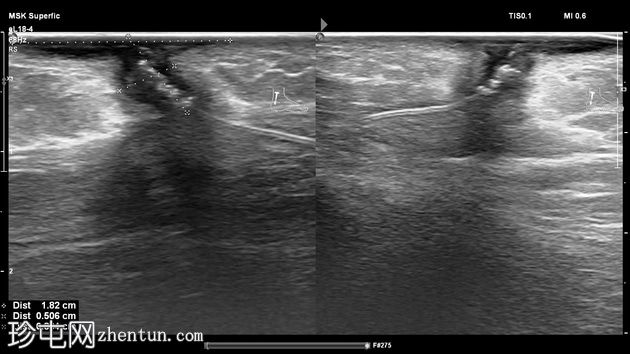

纵位

左足跟皮下组织内可见一管状高回声物质,呈串珠状,与手术缝线相符,周围环绕着低回声积液。与缝线相连的是一根细细的、呈轨道状的高回声合成单丝,它穿过跟腱呈弧形走行,该缝线为不可吸收缝线。